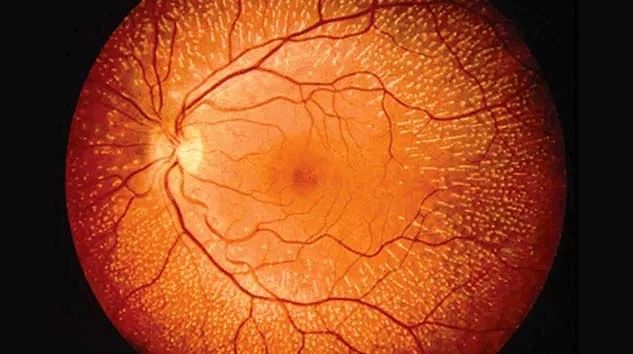

Изображения и анатомия сетчатки глаза

Раздел: Визуальный дайджест